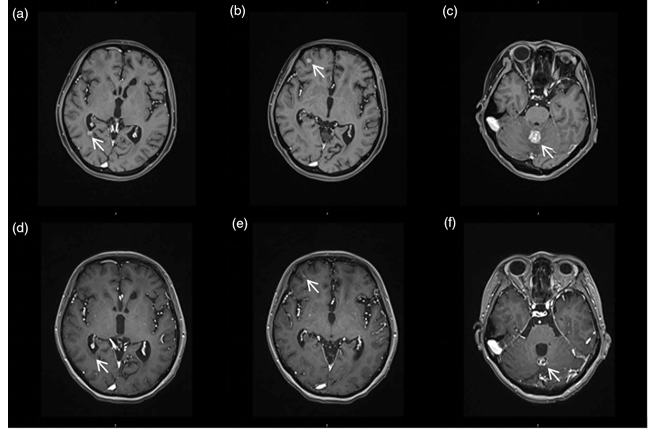

图1. 维迪西妥单抗(RC48)治疗前后的颅脑MRI对比。 A-D:基线期(2021年9月),显示多发强化的脑转移病灶。 E-H:维迪西妥单抗治疗5周期后,病灶显著缩小,评价为部分缓解(PR)。

在完成 5 个周期的治疗后,颅脑 MRI 影像显示多发脑转移结节显著缩小,评价为部分缓解。更具临床意义的是,该患者在 RC48 单药治疗期间,颅内病灶的无进展生存期(PFS)达到了 12 个月,远超既往预期。在安全性方面,患者表现出良好的耐受性,未出现明显相关的毒性或血液学异常,且避免了重复放疗可能带来的神经认知功能受损,保障了较高的生活质量。